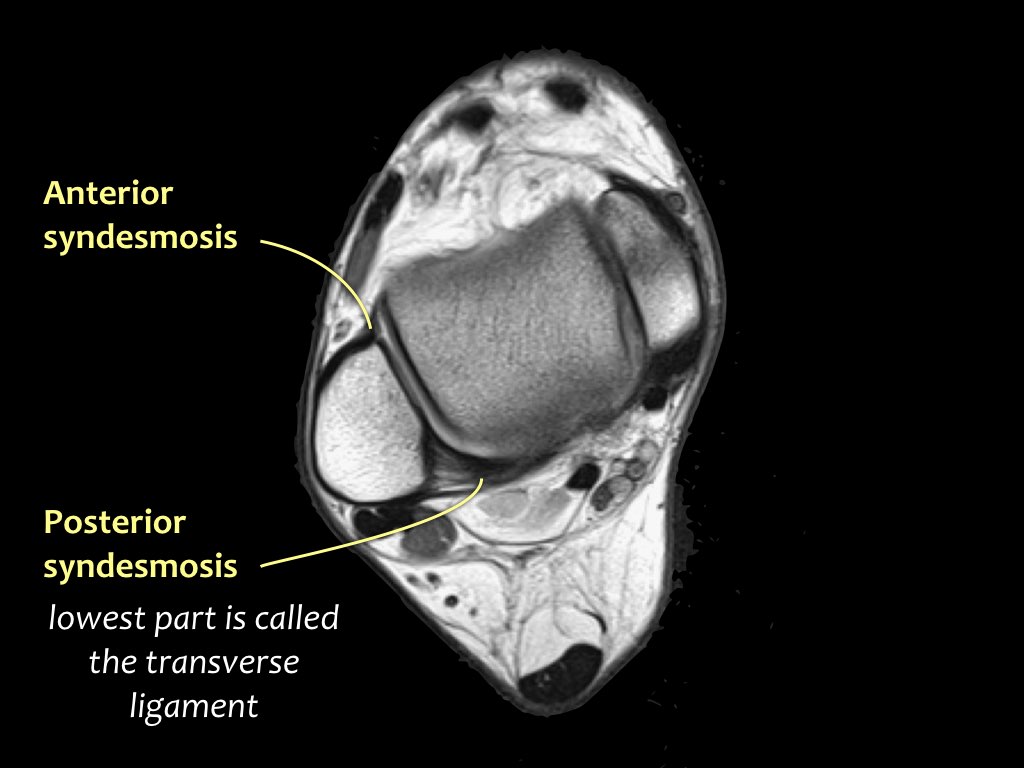

Các khớp chày mác (syndesmosis) được quan sát rõ nhất trên ảnh cắt ngang:

- Dây chằng chày mác trước (anterior tibiofibular ligament) hay còn gọi là khớp chày mác trước (anterior syndesmosis)

- Dây chằng chày mác sau (posterior tibiofibular ligament) hay còn gọi là khớp chày mác sau (posterior syndesmosis)

- Màng gian cốt (membrana interossei), chạy suốt lên đến chỏm xương mác.

Các khớp chày mác thường bị tổn thương trong các chấn thương xoay ngoài, như:

- Gãy xương Weber B (chấn thương ngửa – xoay ngoài theo phân loại Lauge-Hansen)

- Gãy xương Weber C (chấn thương sấp – xoay ngoài theo phân loại Lauge-Hansen)